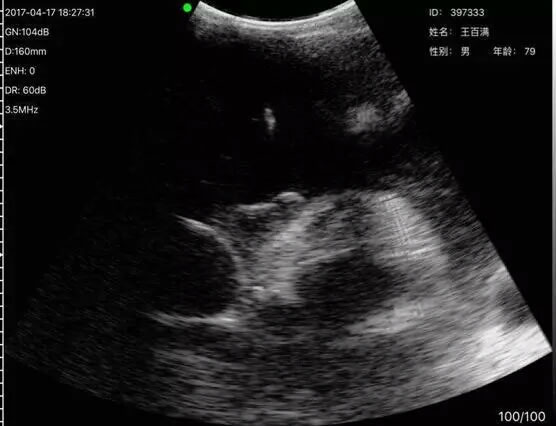

超声成像诊断对重症肺炎的评估、检测具有重要的作用,而掌上超声小巧方便非常适合在抗疫一线使用。

索诺星科技第一时间捐出两套掌上超声给武汉的两家医院,并对抗疫相关的采购需求一律实行只收生产成本的特殊价格政策,力争为此次抗疫做出力所能及的贡献。